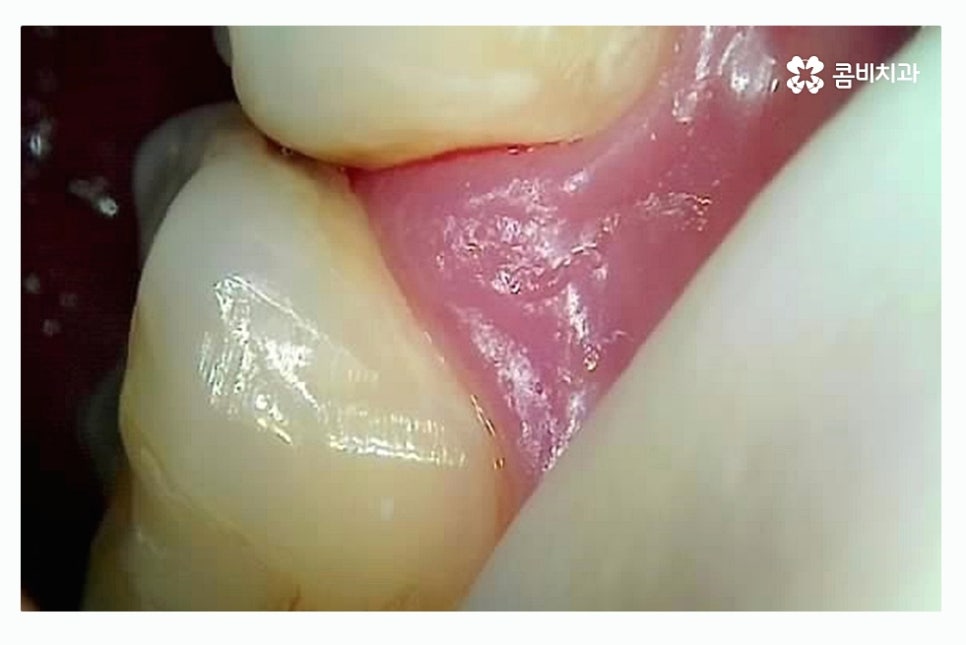

인접면 충치가 발생하는 원인으로는 칫솔질을 보다 꼼꼼하게 해야

하는 부분도 있겠지만 평소 치실을 함께 사용하는 것이

치아 사이에 이물질이 낀 채로 방치되는 것을 줄일 수 있으며

평소 식습관도 영향이 있을 수 있어요.

또한 청결관리를 잘하고 좋은 식습관을 유지하더라도

대부분의 사람들은 치석이 조금씩 쌓이기 때문에 주기적으로

치과 스케일링을 받는 것이 각종 구강질환을 예방할 수 있는데요